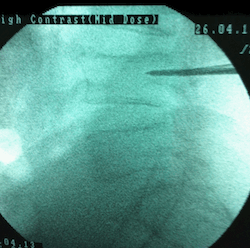

Hastaya uygulama öncesi sakinleştirci ilaç uygulanır. Hasta yüz üstü pozisyonda ameliyat masasına yatırılır. Omurga kırığının yerine göre sırt veya bel bölgesinde girişimin yapılacağı yer steril olarak silinip örtülür. Skopi(X-ışınları kullanarak görüntüleme sağlayan cihaz) kontrolü ile müdahalenin yapılacağı bölge görüntülenir .Girişim noktası saptandıktan sonra giriş noktasına lokal anestezik uygulanır. Bu noktadan küçük bir kesi yapılarak vertebroplasti iğnesi kemikle temas edene kadar ilerletilir ve iğne döndürülerek omurga korteksinin içine girilir. İğne yerleştirildikten sonra sıra kemik çimentosu skopi kontrolü ile sement verilir